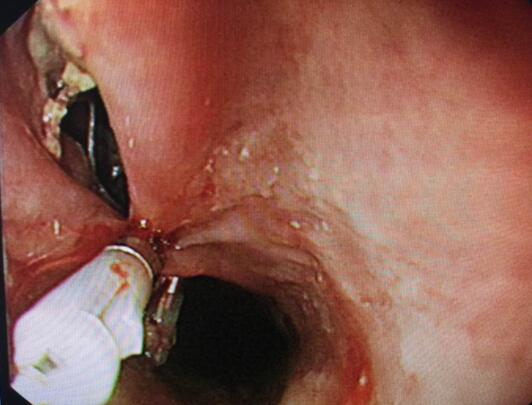

内镜中心王莹副主任考虑到患者病情复杂且高龄,不具备急诊外科手术条件,在确保患者安全情况下行内镜下异物钳取术、钛夹封闭损伤治疗。术中观察到梭形枣核嵌顿于患者食管上端,一侧食管壁可见纵形全层伤口,损伤非常严重。王主任克服困难,以她熟练的操作最终将异物顺利取出。

钛夹逐渐夹闭损伤